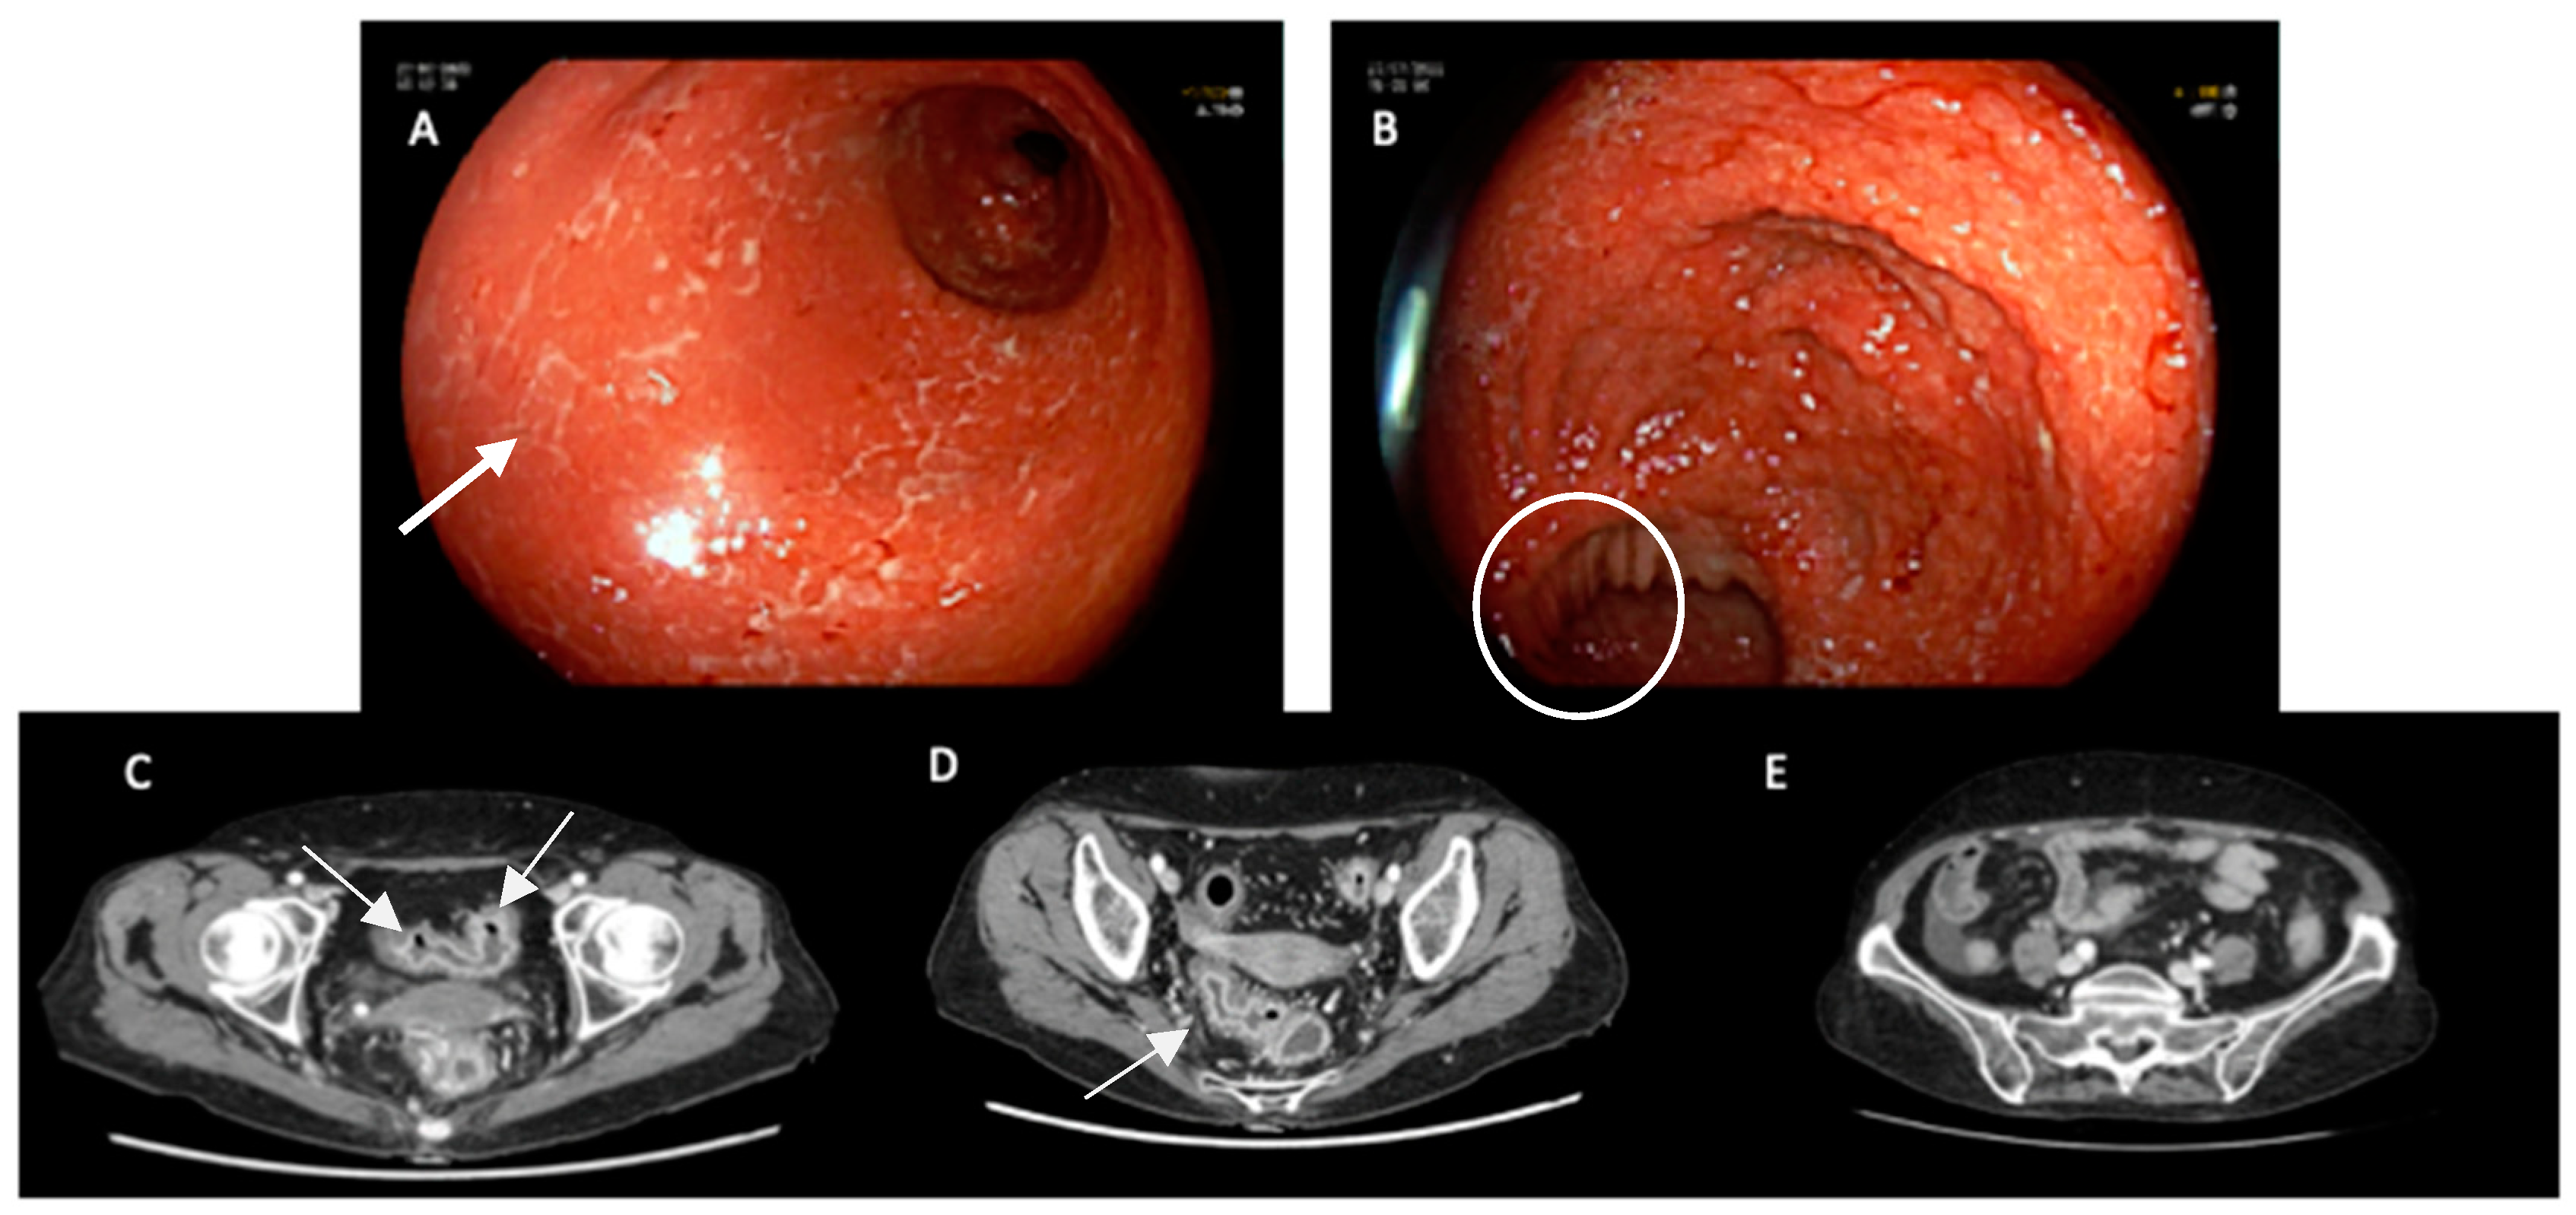

- Gosangi, B.; McIntosh, L.; Keraliya, A.; Irugu, D.V.K.; Baheti, A.; Khandelwal, A.; Thomas, R.; Braschi-Amirfarzan, M. Imaging features of toxicities associated with immune checkpoint inhibitors. Eur. J. Radiol. Open 2022, 9, 100434. [Google Scholar] [CrossRef]

- Barina, A.R.; Bashir, M.R.; Howard, B.A.; Hanks, B.; Salama, A.; Jaffe, T.A. Isolated recto-sigmoid colitis: A new imaging pattern of ipilimumab-associated colitis. Abdom. Imaging 2015, 41, 207–214. [Google Scholar] [CrossRef]

- Garcia-Neuer, M.; Marmarelis, M.E.; Jangi, S.R.; Luke, J.J.; Ibrahim, N.; Davis, M.; Weinberg, J.; Donahue, H.; Bailey, N.; Hodi, F.S.; et al. Diagnostic Comparison of CT Scans and Colonoscopy for Immune-Related Colitis in Ipilimumab-Treated Advanced Melanoma Patients. Cancer Immunol. Res. 2017, 5, 286–291. [Google Scholar] [CrossRef]

- Shieh, A.C.; Guler, E.; Pfau, D.; Radzinsky, E.; Smith, D.A.; Hoimes, C.; Ramaiya, N.H.; Tirumani, S.H. Imaging and clinical manifestations of immune checkpoint inhibitor-related colitis in cancer patients treated with monotherapy or combination therapy. Abdom. Imaging 2019, 45, 3028–3035. [Google Scholar] [CrossRef]

- Durbin, S.M.; Mooradian, M.J.; Fintelmann, F.J.; Zubiri, L.; Chute, D.F.; Kambadakone, A.; Pisuchpen, N.; Reynolds, K.L.; Dougan, M. Diagnostic utility of CT for suspected immune checkpoint inhibitor enterocolitis. J. Immunother. Cancer 2020, 8, e001329. [Google Scholar] [CrossRef]

- Pisuchpen, N.; Durbin, S.M.; Mooradian, M.J.; Fintelmann, F.J.; Reynolds, K.L.; Dougan, M.; Kambadakone, A. Multi-detector computed tomography (MDCT)–based severity score as a prognostic tool in patients with suspected immune checkpoint inhibitor therapy associated colitis. Eur. Radiol. 2021, 31, 8868–8878. [Google Scholar] [CrossRef] [PubMed]